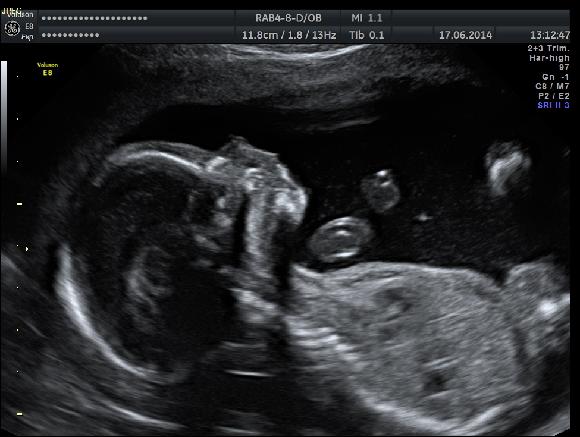

tak vcera jsem byla na kontrolnim velkem ultr.a vse  ok!Hlavne u paní doktorky,která mě uklidnila,že velikost nožek je normální,že pan doktor rád přehání.Jen teda určila,že mimi bude o týden mladší.Takže sem spadla na 19.tt ale to neva.Malé zjistila na mozku cystu ale to že se vstřebá a nic to neznamená,žádná nemoc ani vada,jen tam musím na ult.ještě v 25.tydnu.

Přikládám fotku ze včerejška:)